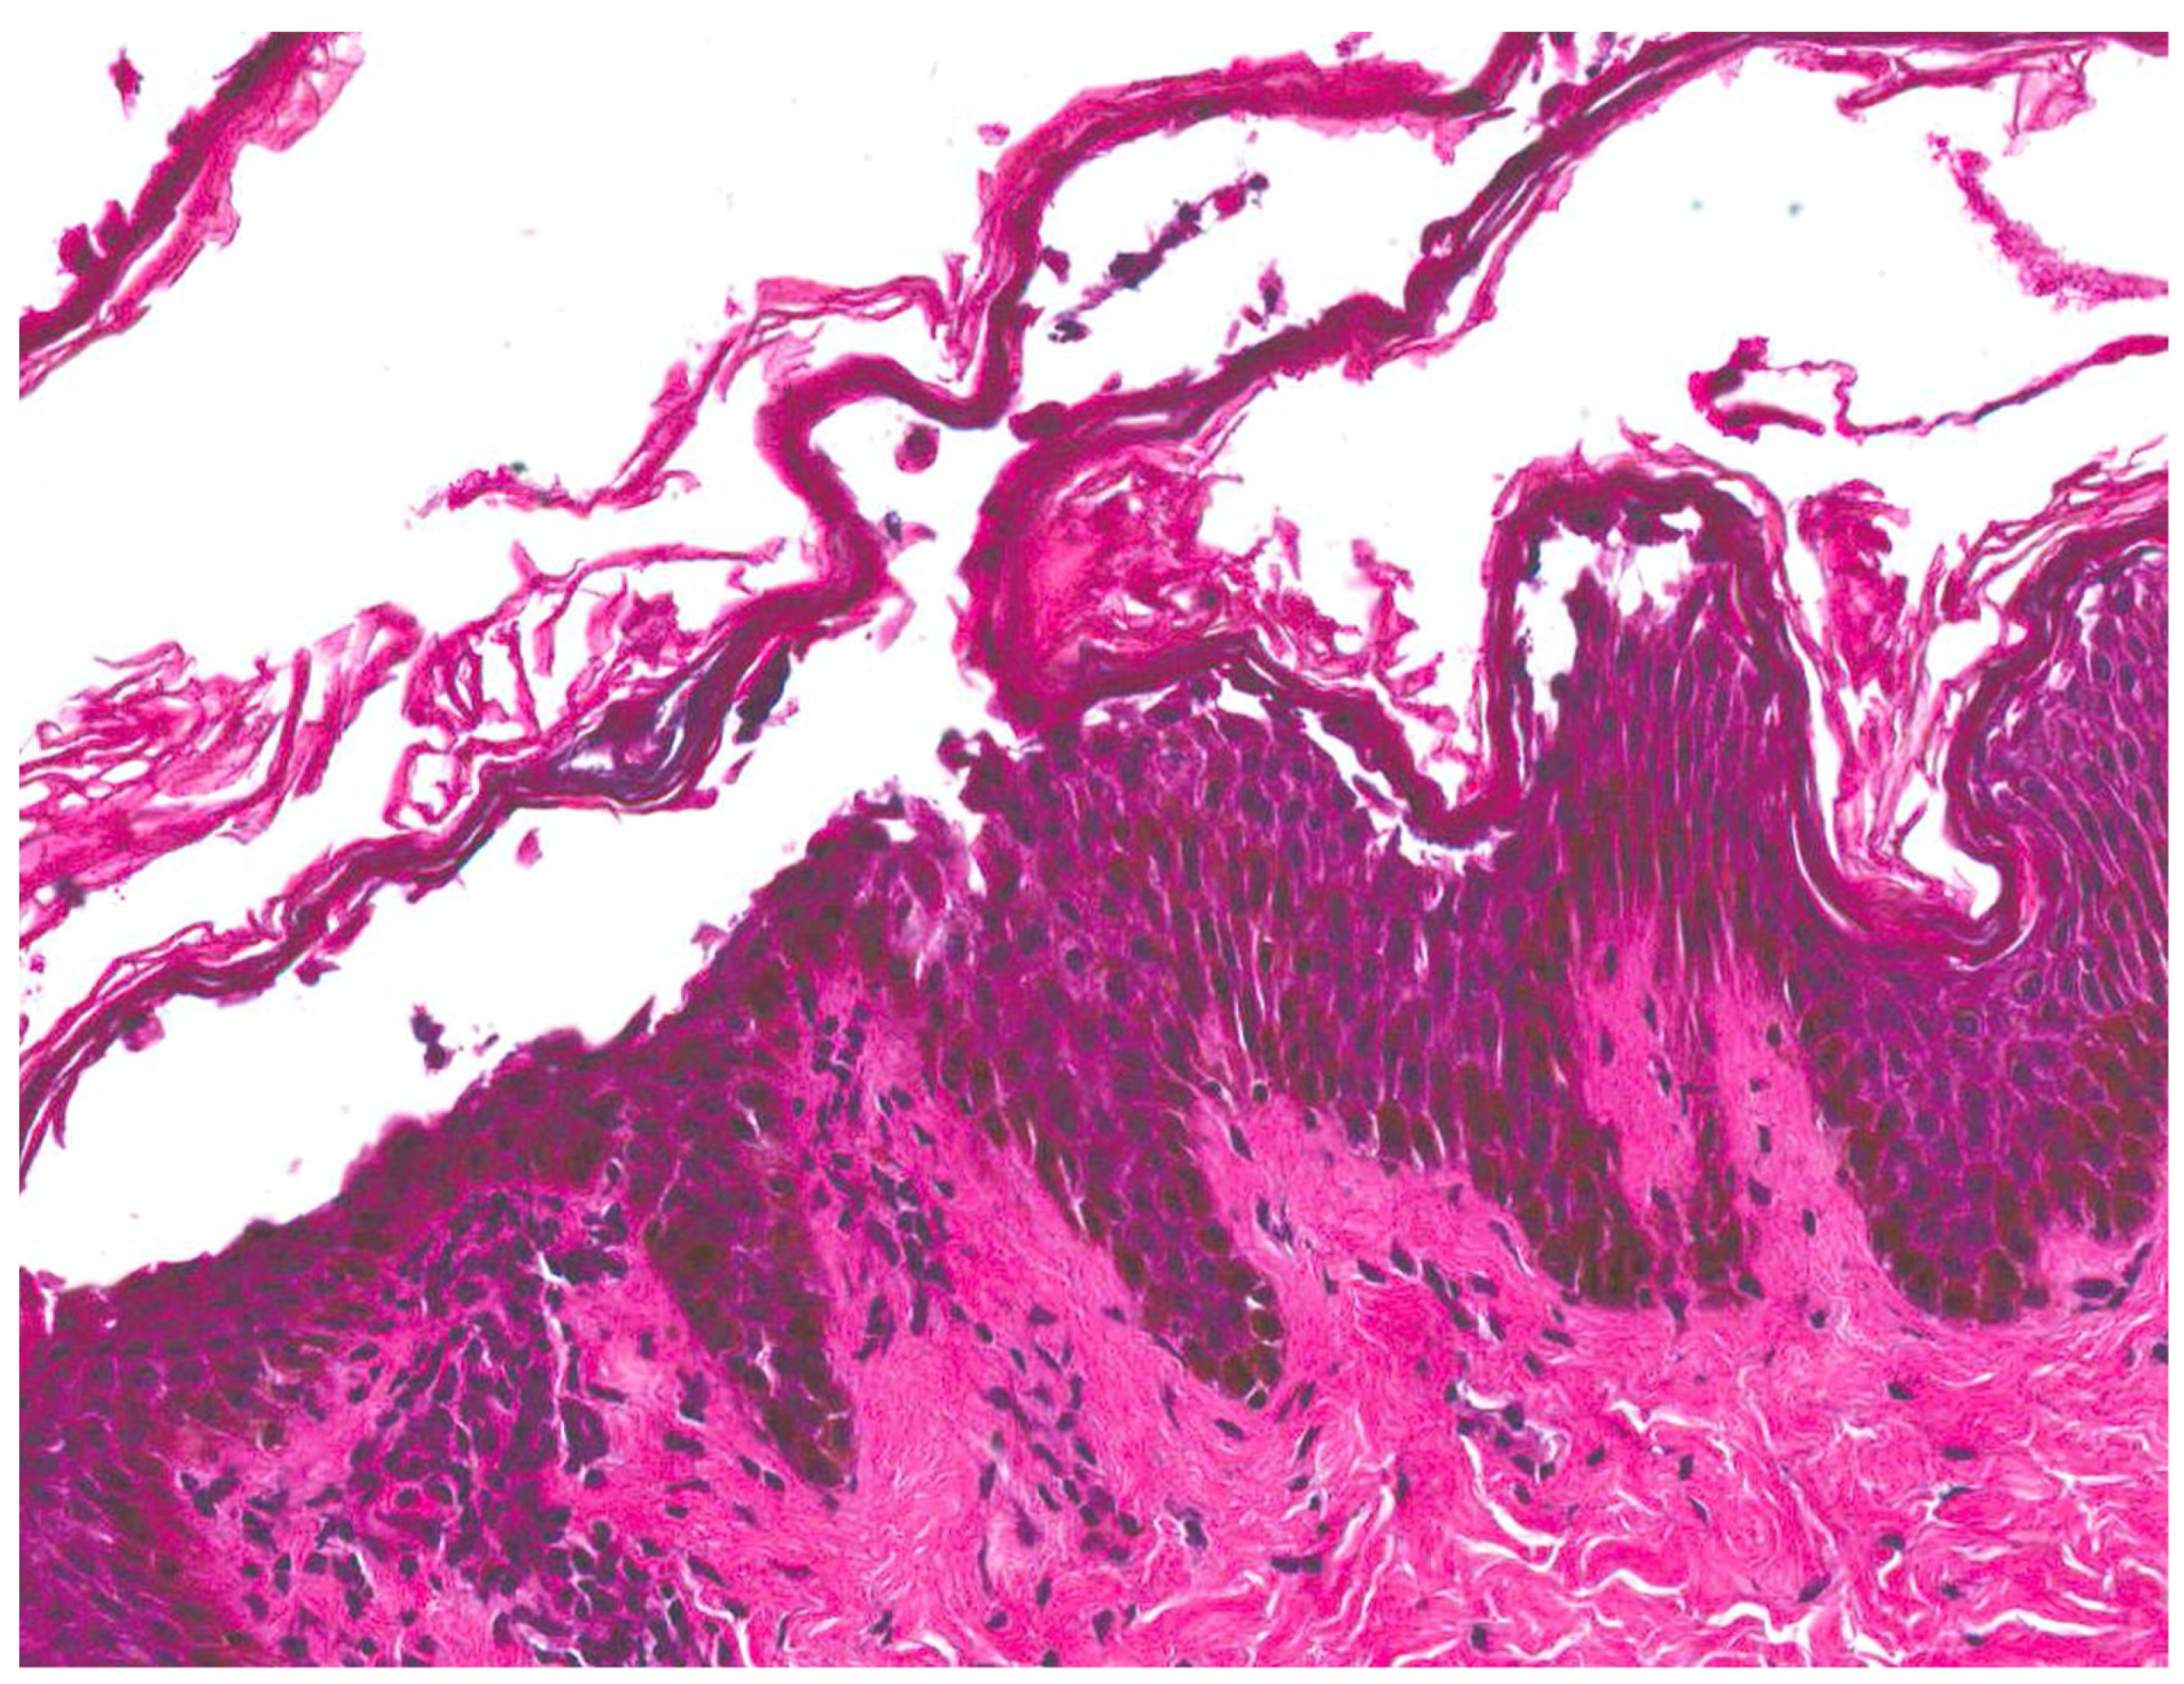

| Staphylococcal scalded skin syndrome (SSSS) [1,2,3,4] | Most commonly seen in children under the age of six | Initial localized infection by S. aureus | Prodrome of irritability, generalized fatigue, and fever followed by the progression of skin lesions. Positive Nikolsky sign | Superficial intraepidermal cleavage beneath the stratum corneum | Within 24–48 h, tender erythematous patches develop. Several hours later, fragile blisters develop within the areas. The blisters progress to form bullae, which rupture easily and then desquamate. |

| Bullous impetigo [4,15] | Newborns and infants most commonly affected | Caused by S. aureus production of exfoliative toxins which cleave DSG1 resulting in acantholysis and bullae formation | Small vesicles that grow into tense bullae that rupture and leave behind a narrow rim of scale. The bullae appear in well-demarcated clusters at the initial site of infection. Systemic involvement is rare. Nikolsky sign is negative and culture of bullae or erosions is positive | Loss of cell adhesion in the superficial epidermis (granular layer) resulting in a subcorneal blister; mixed dermal inflammatory infiltrate, crusting, epidermal hyperplasia, and lesional cocci in clusters | Usually resolves within 3–6 weeks. However, high risk patients may develop SSSS due to dissemination of exfoliative toxin |